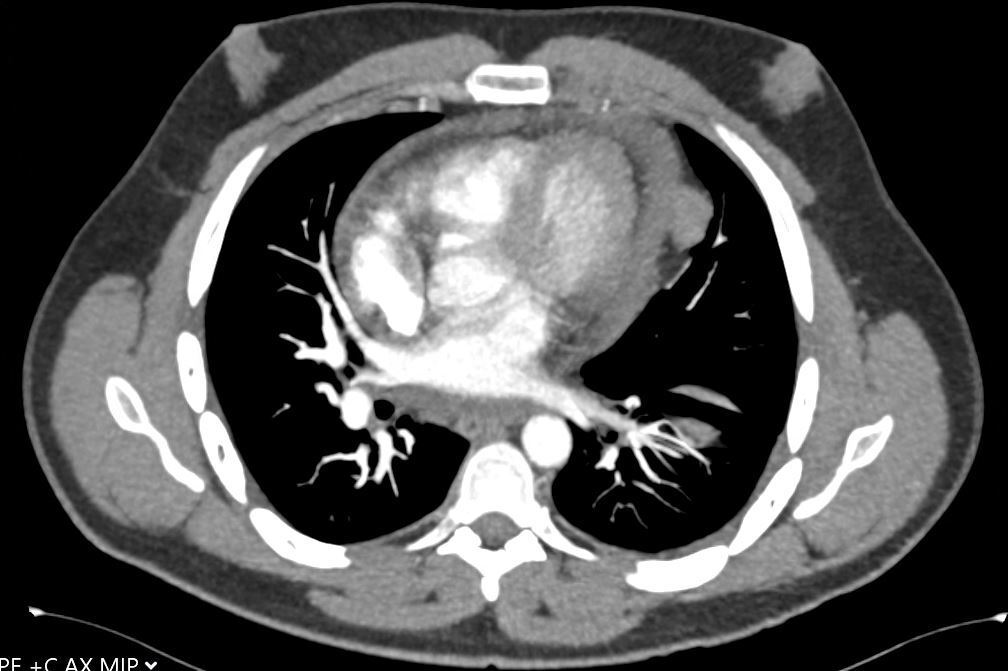

A 30-year-old man presents with dyspnea and is found to have an anterior mediastinal mass, as well as supraclavicular lymphadenopathy; biopsy of the mass is consistent with thymic carcinoma. Imaging shows his anterior mediastinal mass, lung and diaphragmatic lesions consistent with metastatic malignancy, and probable pericardial involvement with small pericardial effusion (Figures 1, 2, 3, and 4).

Fig. 2: CT image showing large mediastinal mass found to be thymic carcinoma. -

Fig. 3: CT image showing large mediastinal mass found to be thymic carcinoma. -

Fig. 4: CT image showing small pericardial effusion. -